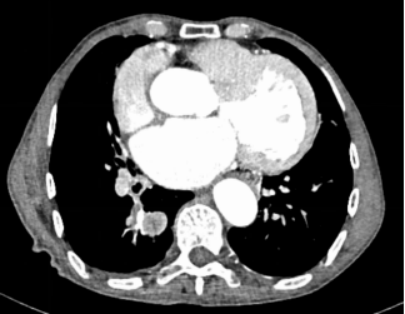

患者王公公,男,78岁,主因“咯血4+天,加重3+小时”于 2021-12-09入院。入院予以止血、对症等治疗。2021-12-09胸部CT、支气管动脉成像:右肺下叶后基底段结节影,考虑周围型肺癌可能性大;支气管动脉成像:右侧支气管动脉稍增粗。

2021-12-26行胸部CT、支气管动脉成像:

1、双肺炎变,右肺上叶空洞形成,考虑继发性肺结核伴空洞形成可能。

2、右肺上叶支气管扩张。

3、右肺上叶支气管动脉增迂曲;主动脉钙化。